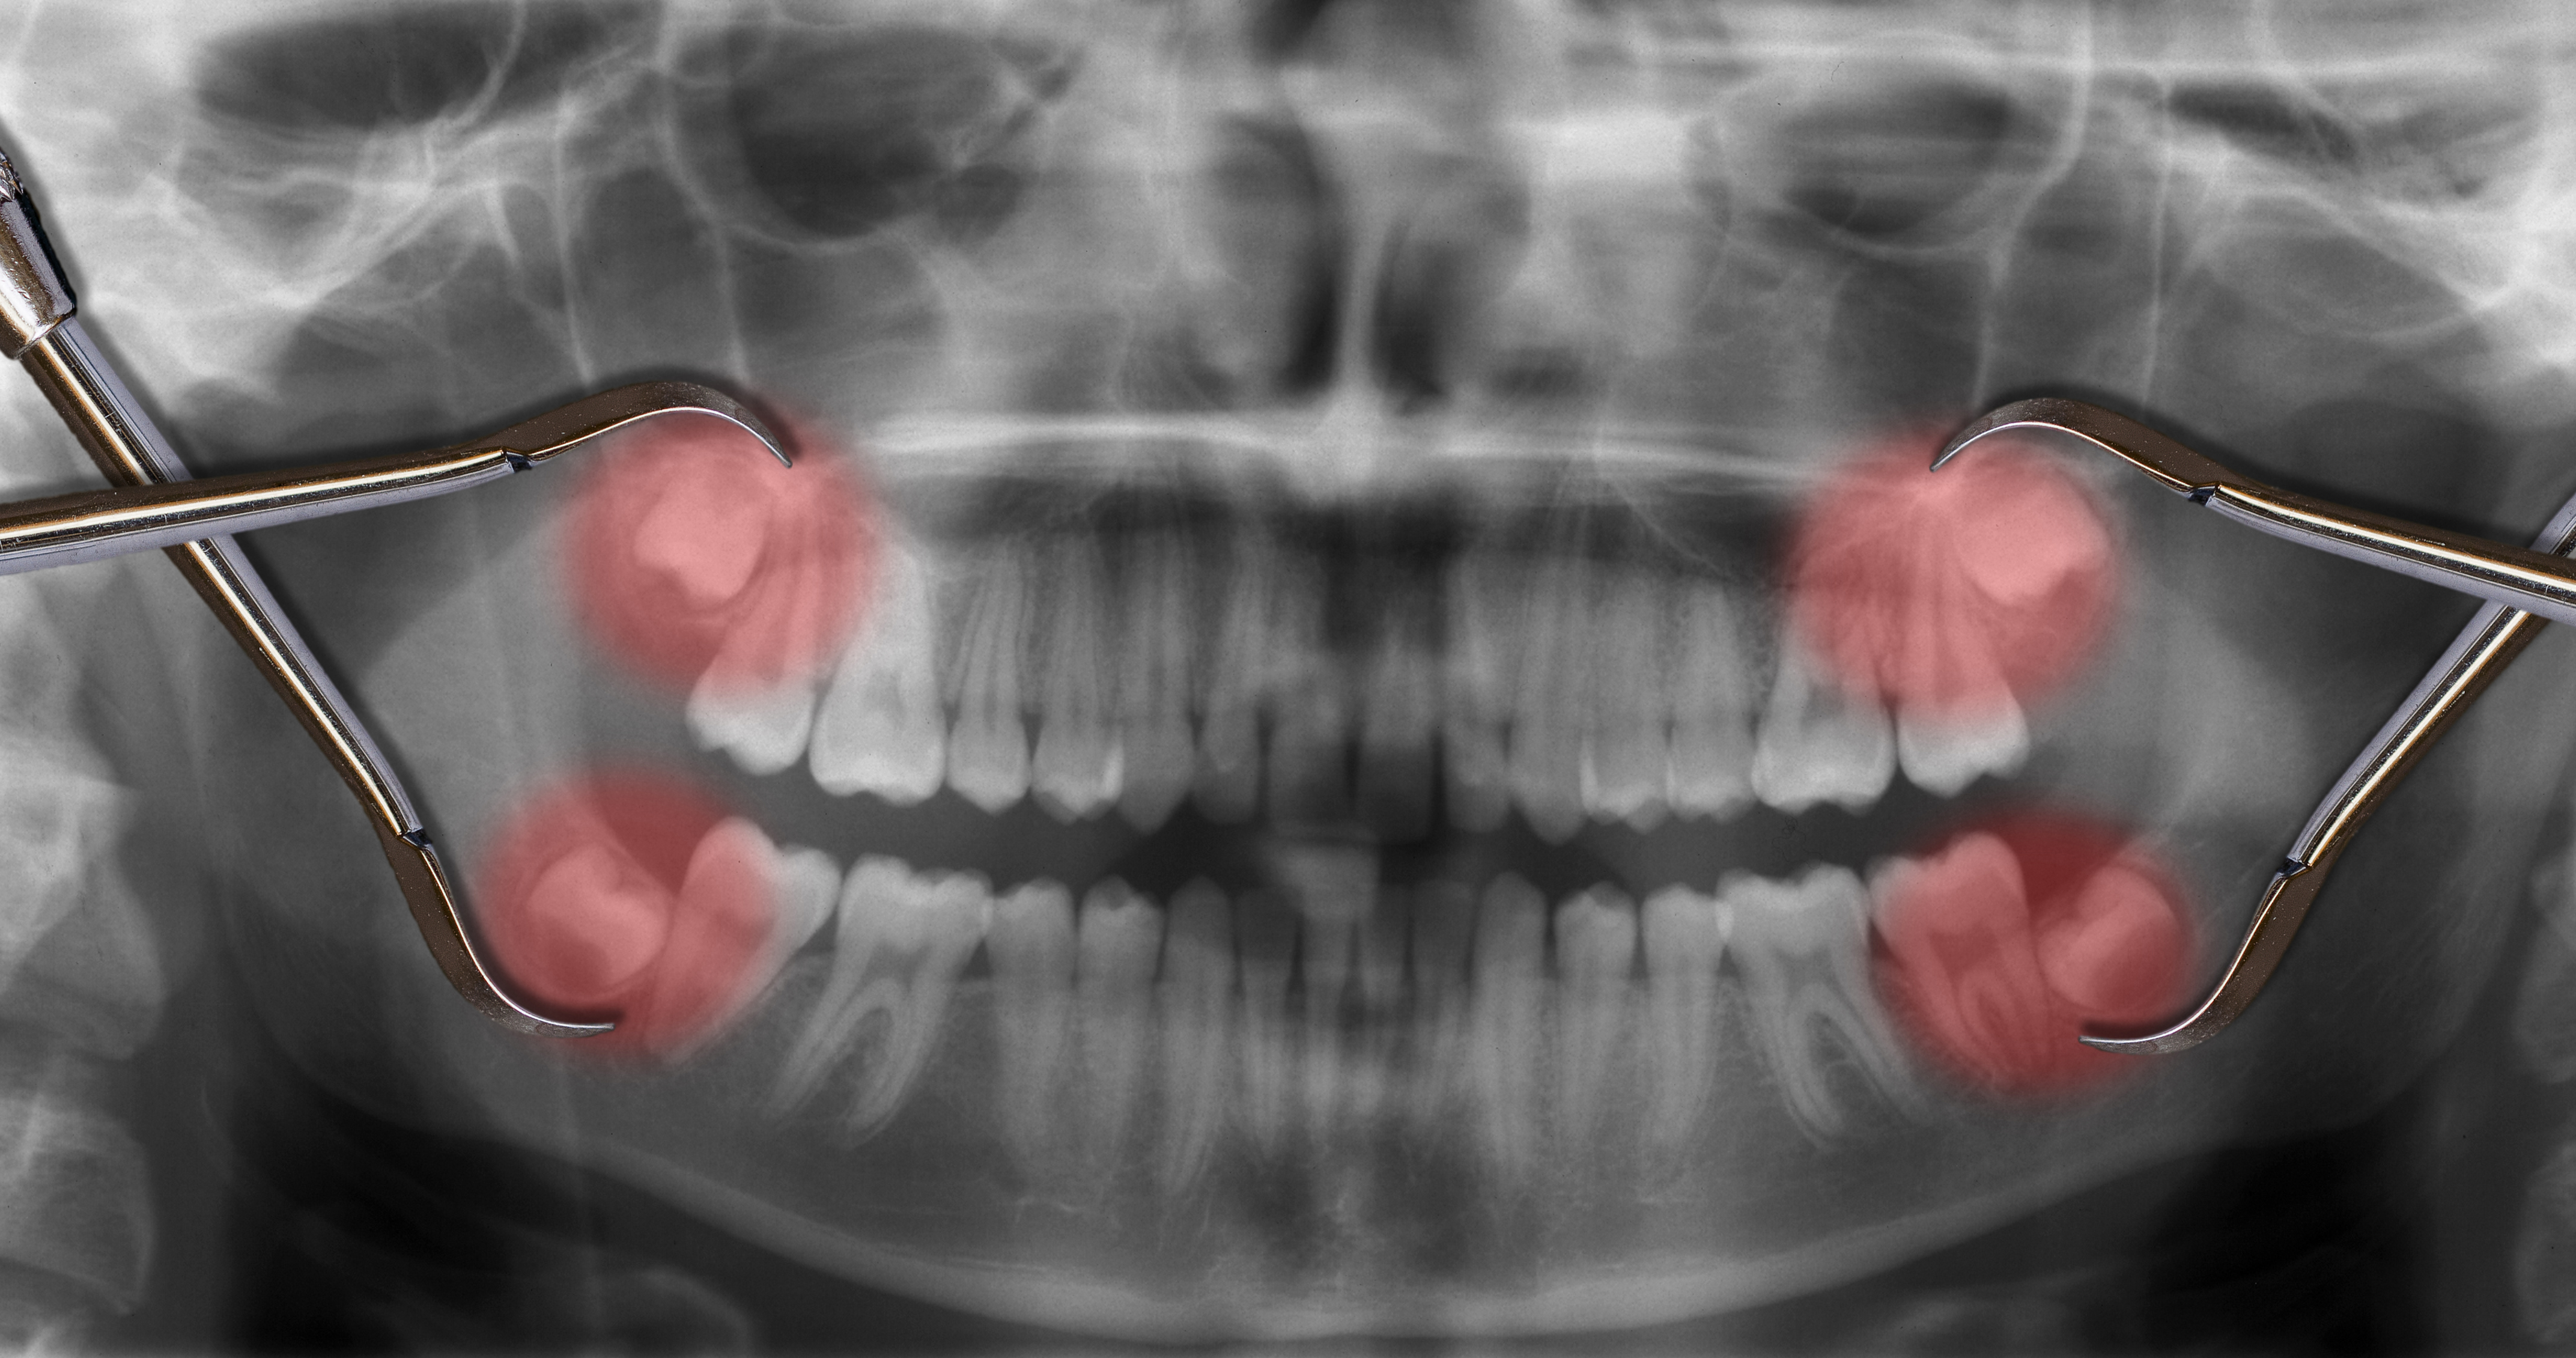

C. Extraction: the removal of a tooth. This typically is executed on teeth which are difficult, diseased, or redundant (that is the case for wisdom enamel that don't have any area to grow at the modern-day jaw). They’re commonly eliminated through pulling or cutting. A few even have their expertise tooth removed earlier than they erupt and develop problematic.

The handiest form of this dental surgery process, teeth pulling, is one of the most common offerings of the dentist. It could be executed with nearby (numbing your mouth) or fashionable (putting you to sleep) anesthesia. The reducing version of enamel extraction typically involves impacted understanding tooth determined beneath the gums, so surgical procedure is worried.